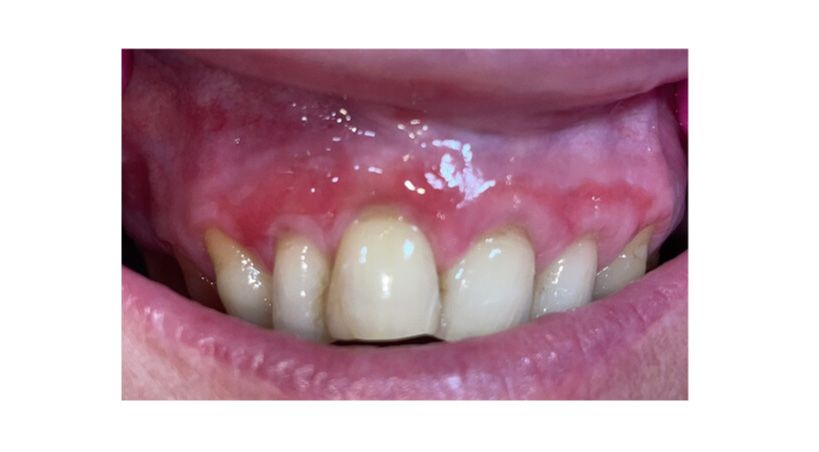

Materiales restauradores bioactivos en odontología

Una revisión integral de los mecanismos, aplicaciones clínicas y direcciones futuras